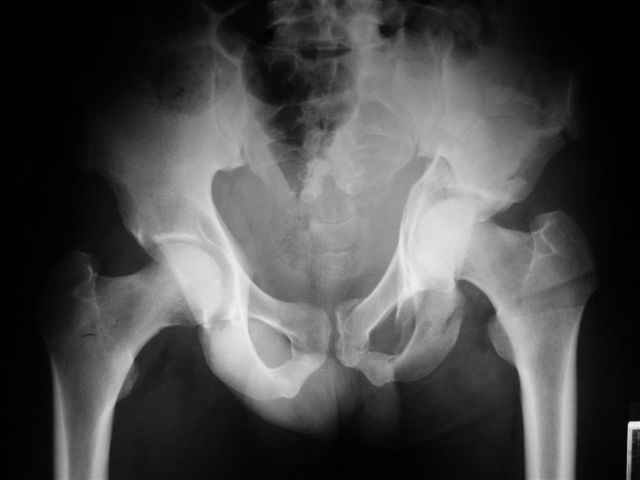

Уважаемые коллеги, 43 летний мужчина, попав в автоаварию 13.10.2004, получил оскольчатый перелом обеих колонн левой вертлужной впадины.

общее состояние стабильное, повреждений внутр. органов и нейро-сосудистых нарушений не отмечено. Заранее признателен за советы и комментарии экспертов. Евгений И. Чекашкин